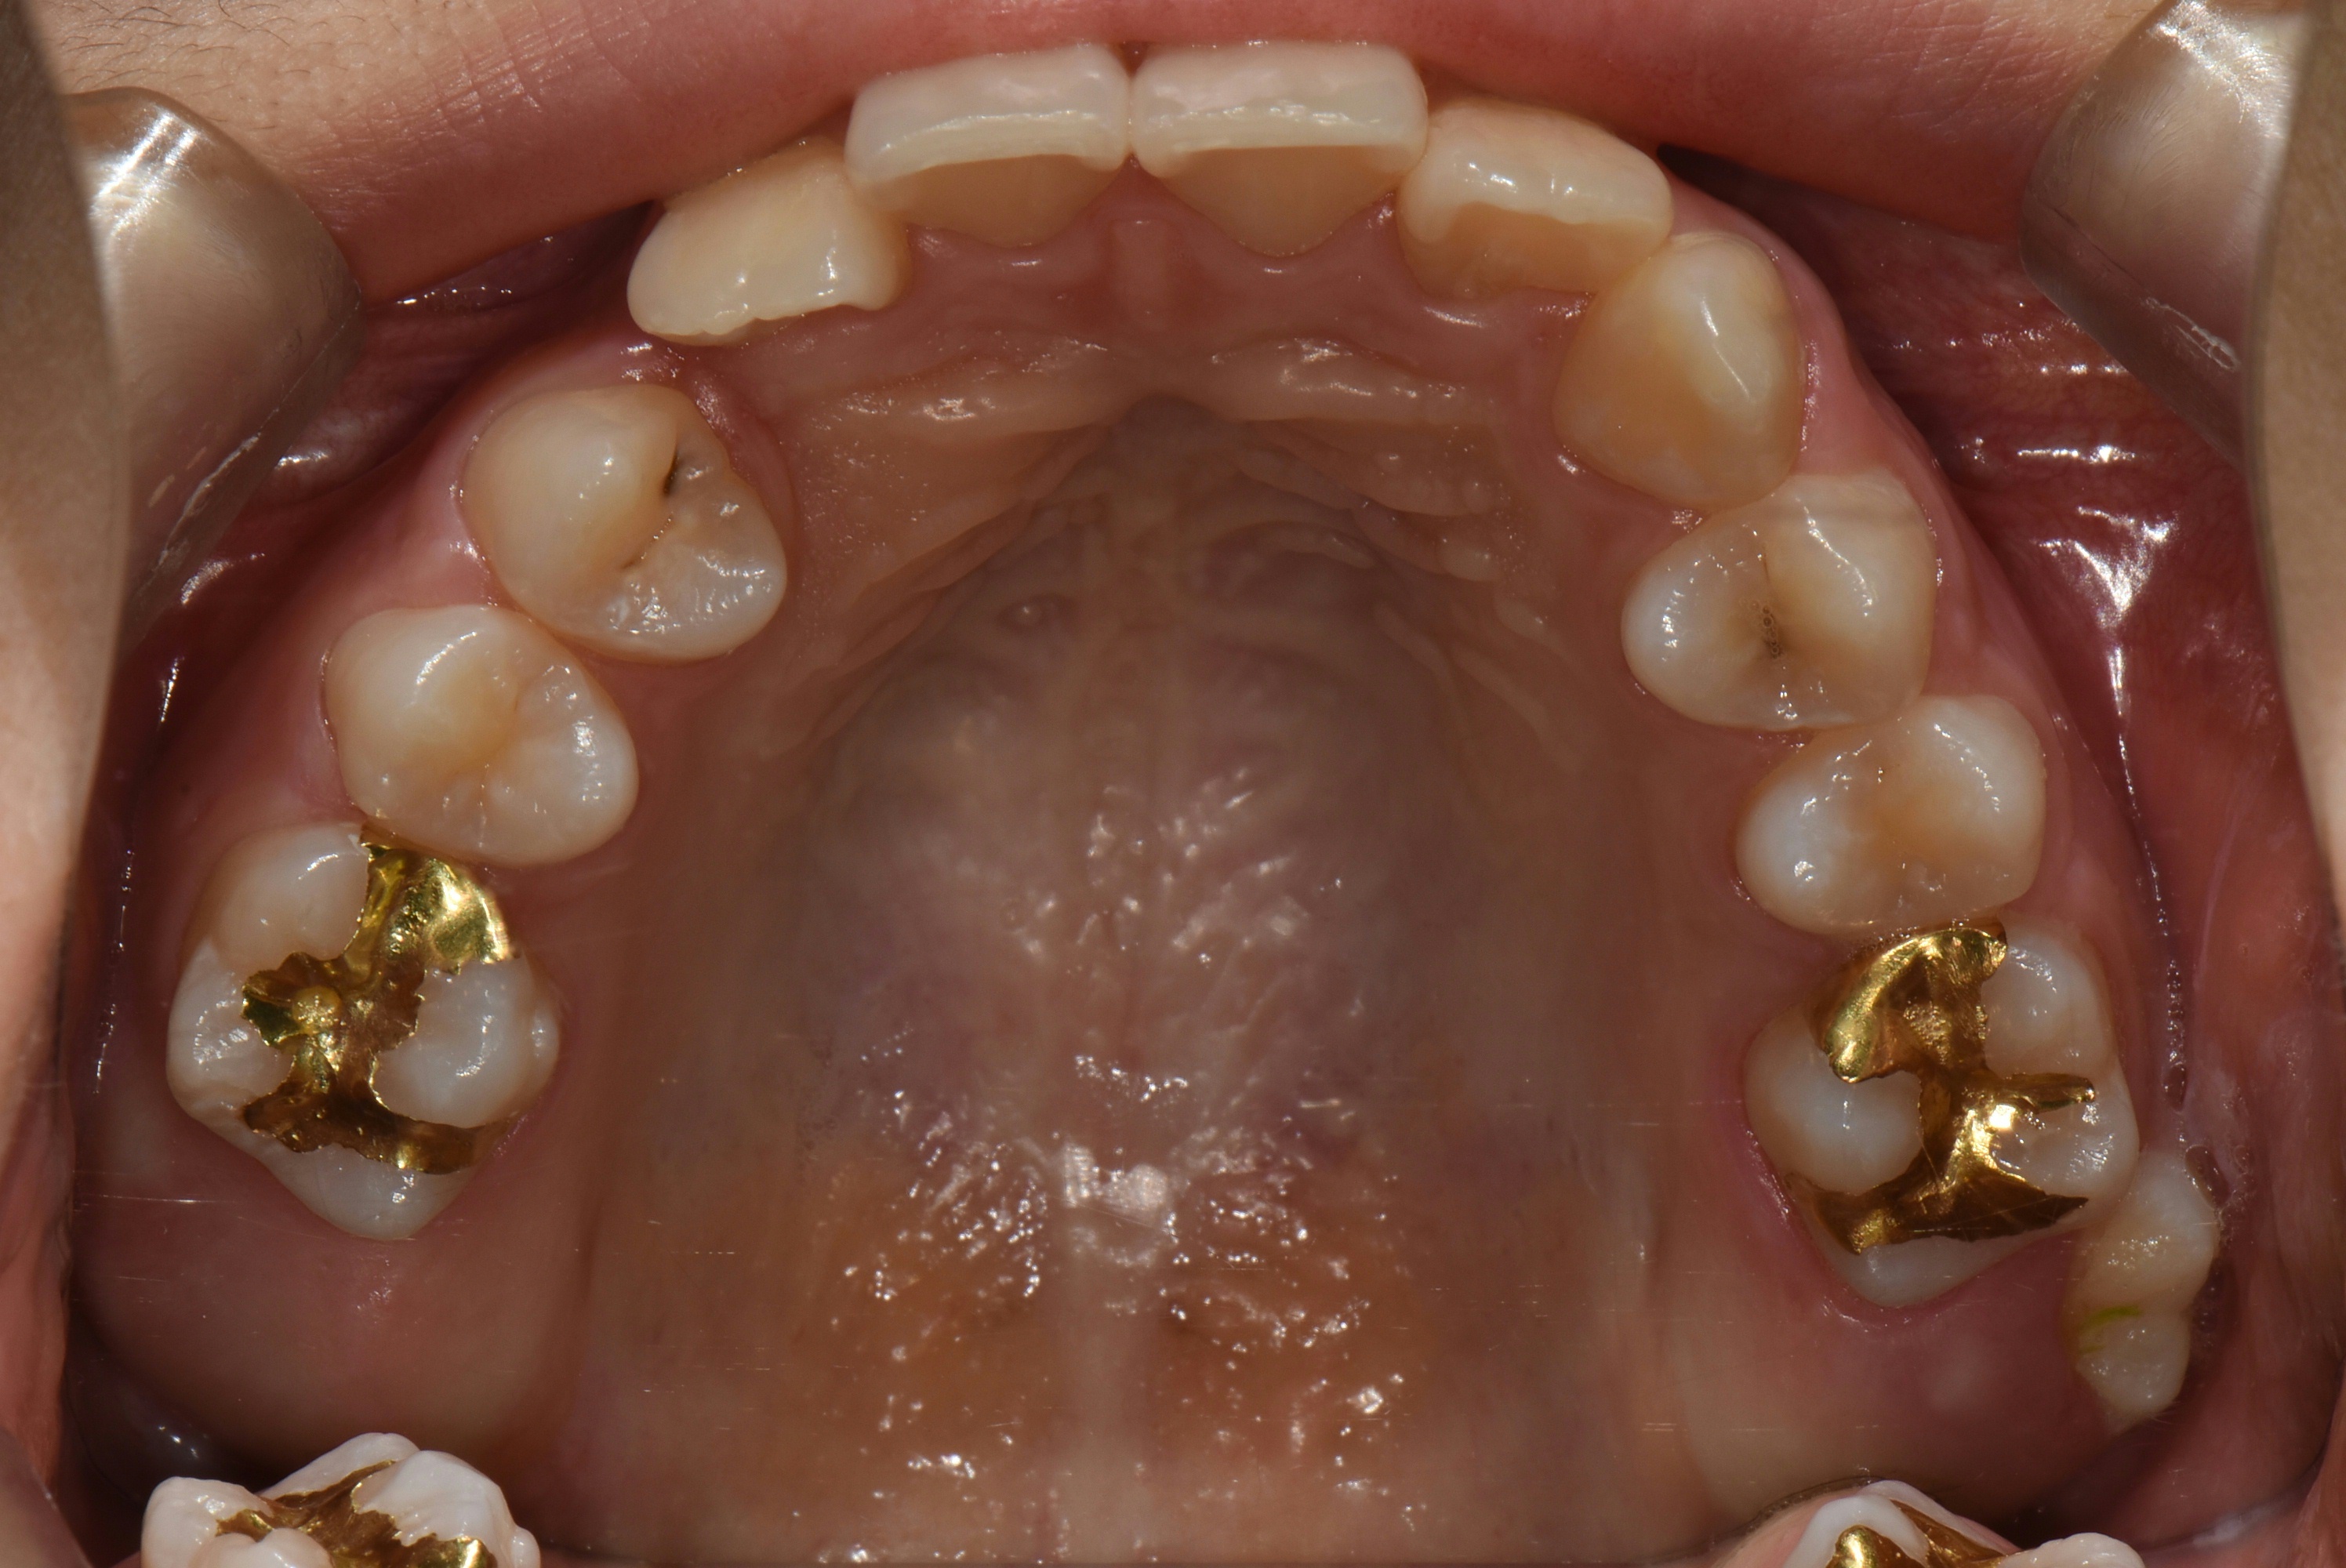

치료 전 사진입니다.